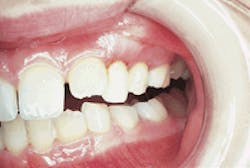

Examination of the head and neck regions revealed no abnormalities present. All vital signs were within normal limits. Oral examination revealed shiny gingiva with a lack of stippling in the area of involvement (see photo). A panoramic radiograph revealed significant bone loss around the maxillary left primary molars (see radiograph).